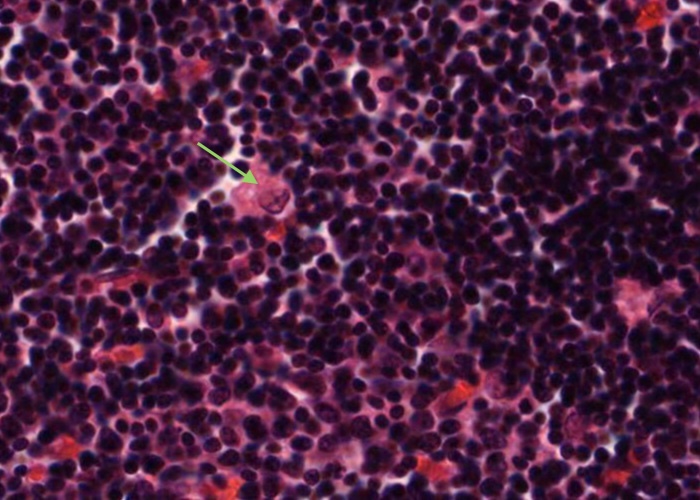

Each type II epithelioreticular cell has a pale-stained nucleus and lies within the parenchyma of the cortex. Their cytoplasmic extensions join (via maculae adherents) with other type II cells and they compartmentalise the developing T- cells and also participate in their development.